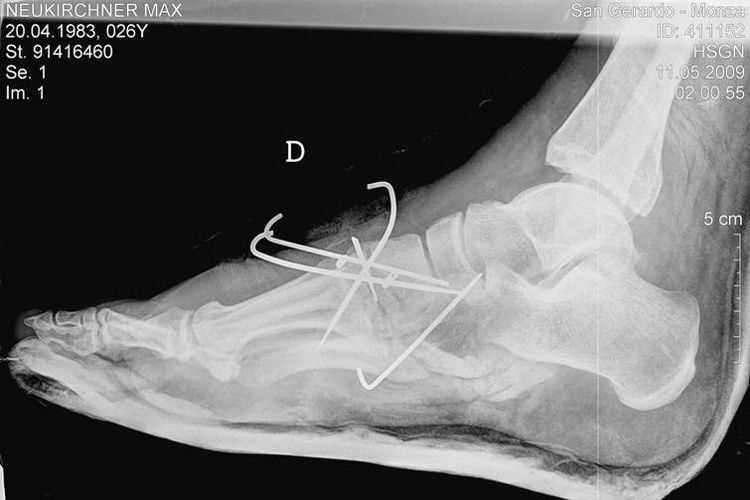

Neukirchner: Fussbrüche schlimmer als erwartet

Max Neukirchner wird morgen in ein deutsches Krankenhaus verlegt. Die Brüche in den Füssen sind schwerwiegender als gedacht.

Max Neukirchners rechte Körperseite wurde bei dem Unfall in Monza schwer lädiert. Neben einem einfachen Oberschenkelbruch zog er sich einen doppelten Wadenbeinbruch und mehrere Brüche im Fuss zu. Der Oberschenkel wurde mit einem Marknagel fixiert, die Brüche im Fuss verdrahtet.